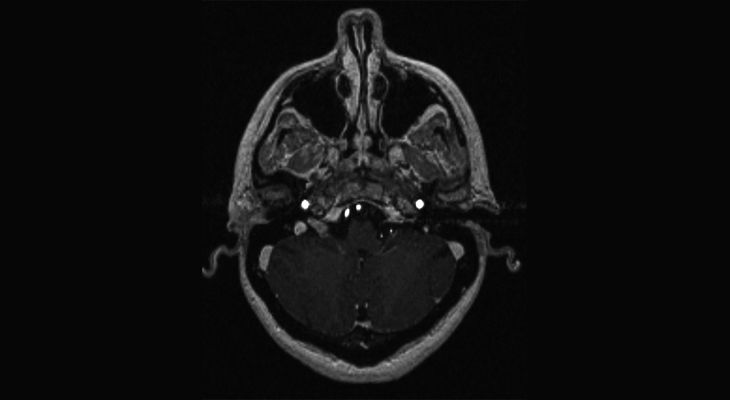

A healthy 45-year-old woman undergoes an MRI for persistent headaches. The headaches resolve with conservative management. However, there is an incidental finding on the MRI of a homogeneously enhancing mass in the right jugular foramen.

What is your diagnosis?